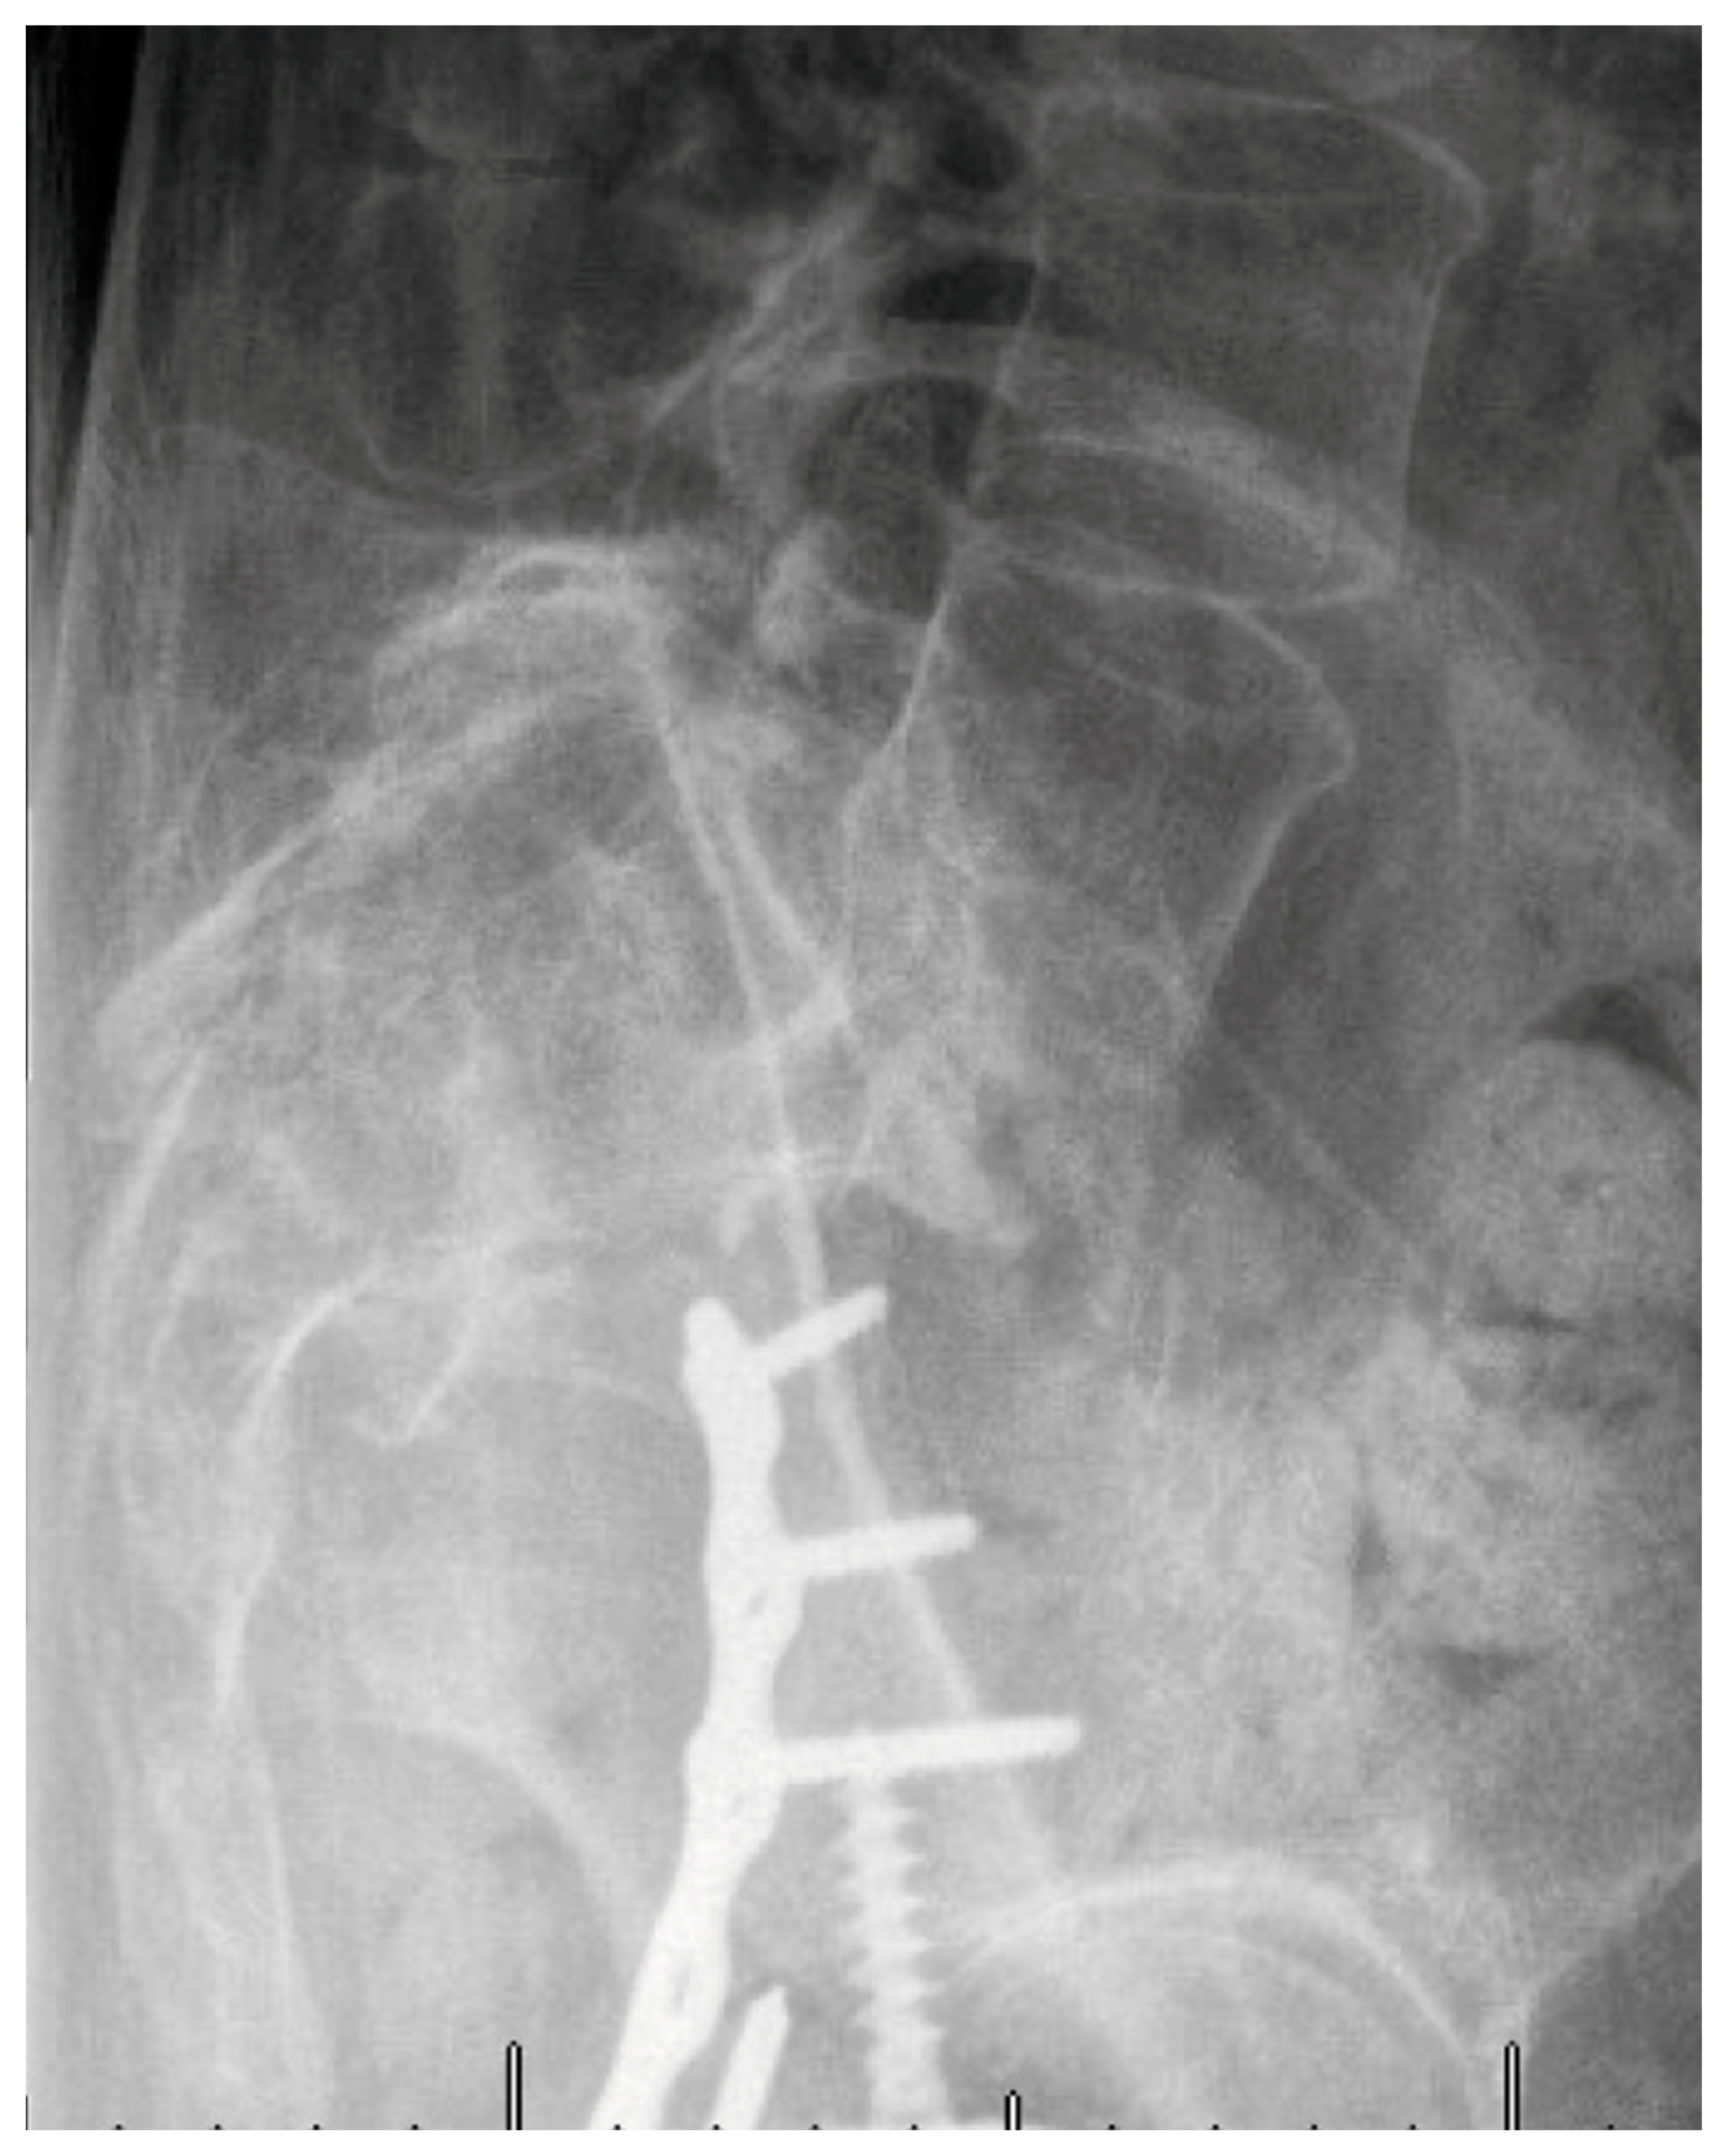

5. Techniques and Considerations in Spinopelvic Fixation: Sequence, Reduction, and Avoiding Complications

6. Spinopelvic Fixation Percutaneous Technique

7. Tran-Sacral Percutaneous Technique